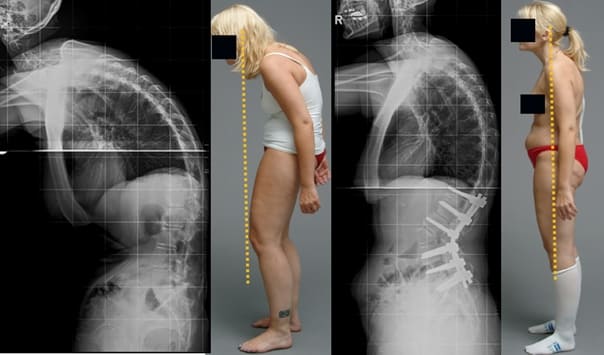

Mujer, 62 años. Luxación grave de vértebras. Hondrodox restauró completamente la columna en 2 cursos.

Mujer, 42 años. Deformación severa de la articulación de la rodilla, rodillas cóncavas. El curso de Hondrodox requirió 2 cursos para la recuperación completa.

Hombre, 37 años. Corrección completa de la postura con Hondrodox en 1 curso.

Mujer, 51 años. Joroba de viuda y deformación de la columna. Eliminación completa de la joroba tras 1 curso de Hondrodox.